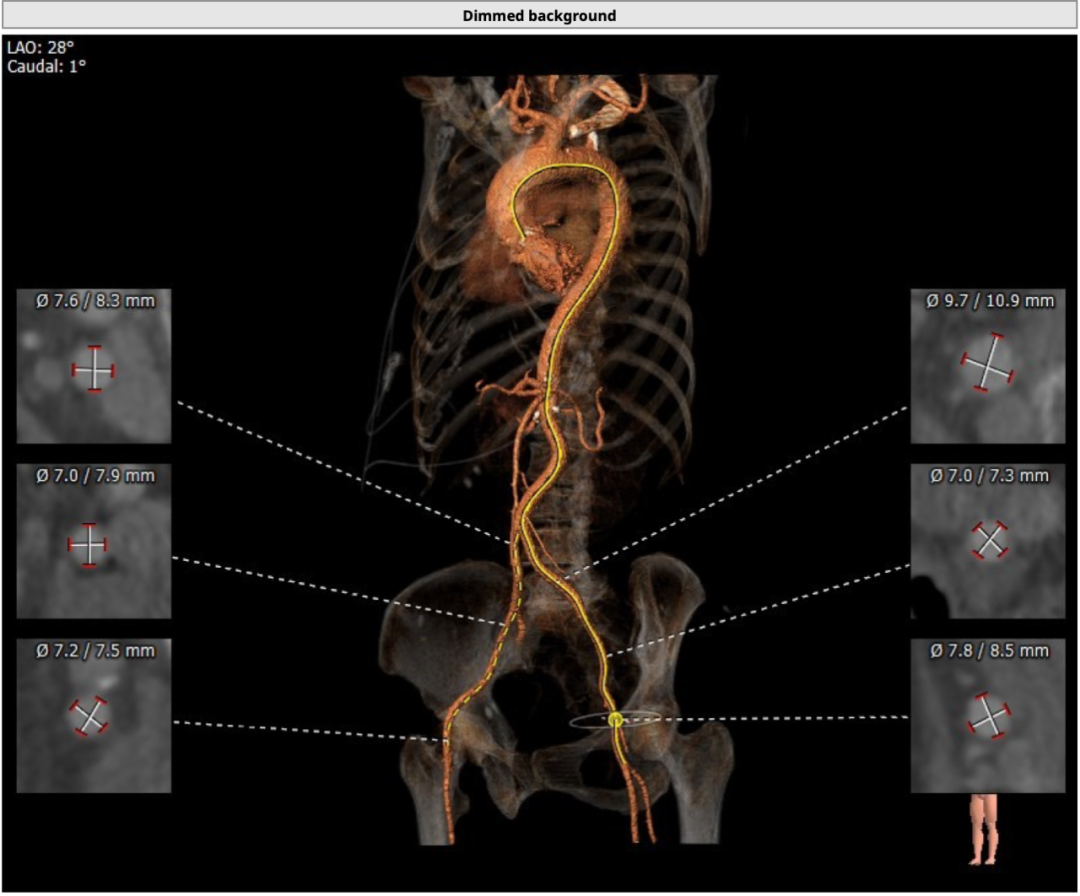

双侧股动脉最小直径均在7mm以上,条件良好。

12.png

外周CT分析情况